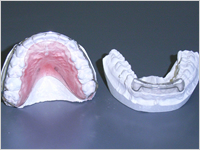

検査で採った歯型を作り、レントゲンなどと併せて分析を行います。

検査で採った歯型を作り、レントゲンなどと併せて分析を行います。 - 診断・治療方針の決定

装置の種類によりますが、装置を付けるための準備をしたり、装置のための歯型を採ります。

装置の種類によりますが、装置を付けるための準備をしたり、装置のための歯型を採ります。 - 装置の装着